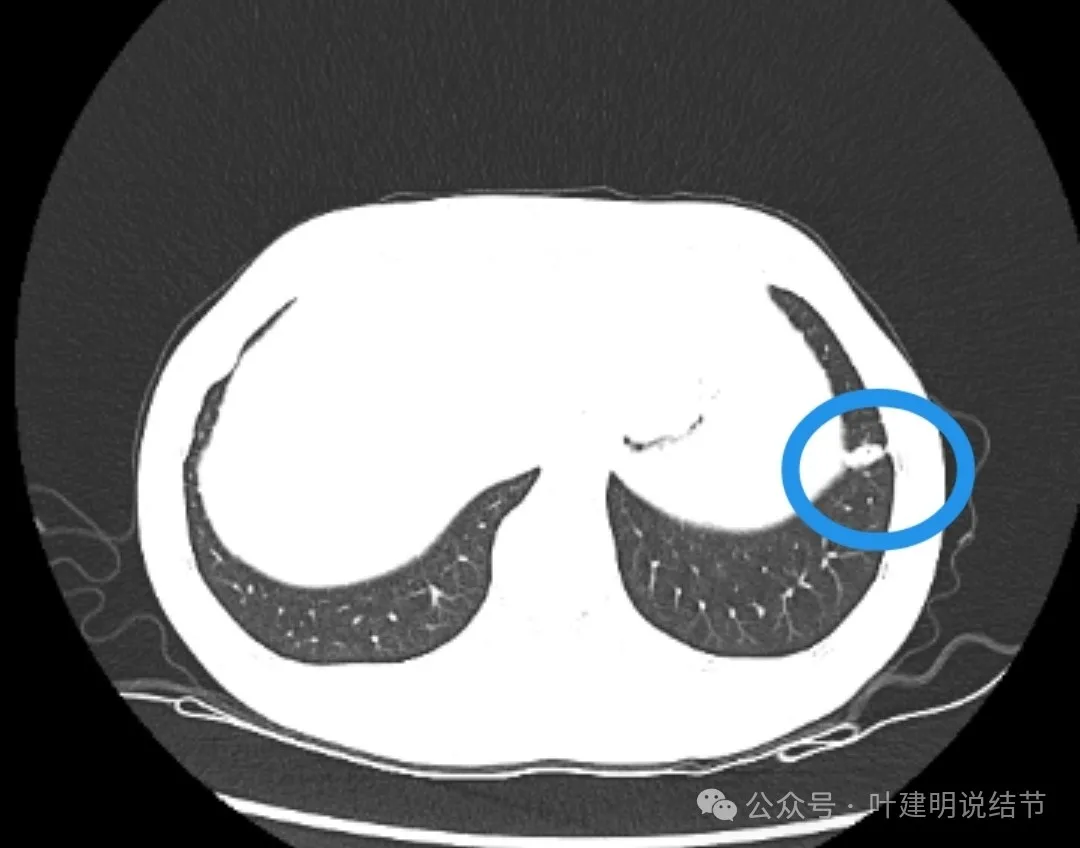

影像展示与分析:

左下叶主病灶实性,收缩力较弱,胸膜略有牵拉,表面似乎较为光滑,毛刺不明显,血管征不明显,整体密度显得较高。

纵隔窗可见。

局部放大了看,边缘略毛糙;胸膜略牵拉;灶内有小区域密度偏低的空泡或偏低密度区;表面似有较为勉强的分叶征的样子。但整体说不上明显收缩力,磨玻璃成分也不大明显。

我看有所异常的就是这几处(次要病灶未展示)。桔色圈起来的过小过淡的磨玻璃结节,考虑肺泡上皮增生可能性大,感觉没到不典型增生,先年度随访;黄色圈起来的微小实性,考虑良性的;蓝色的这处密度高,似乎良性的可能性大,但一是随访有增大,二是有胸膜牵拉,三是位置好,而若真恶性,实性风险大。我个人倾向4-6个月后左下叶靶扫描下,如果有恶性可能,则还是手术切了化验比较放心。意见供参考!